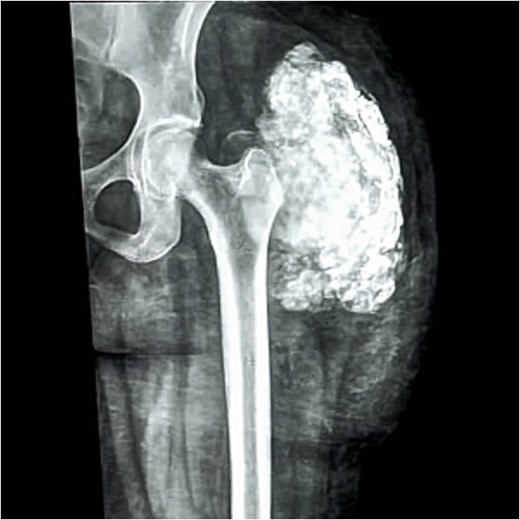

Blood tests: Complete blood count, viral screening, and renal function tests, including S. Phosphorus and S. Calcium, were all within normal range. Radiologically: The X-ray of the left upper thigh and hip shows a “cloud-like” calcified mass with a well-defined margin seen abutting the hip joint (Fig. 1). This was associated with typical “chicken wire” pattern calcification surrounding the soft tissues that were otherwise unremarkable without any bone involvement, fracture, or any other sign of aggressiveness in the form of bony destruction or periosteal reaction. Plain chest X-ray and abdominopelvic US were unremarkable. Local ultrasound examination showed a well-circumscribed echogenic mass splaying soft tissue planes. However, due to resource limitations, advanced cross-sectional imaging such as computed tomography (CT) scan or magnetic resonance imaging (MRI) was not performed.

The X-ray of the left upper thigh and hip shows a calcified mass with a well-defined margin (“chicken wire” pattern calcification).